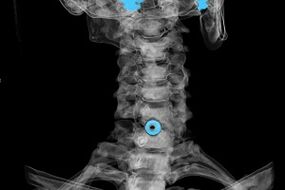

De diagnose wordt gesteld op basis van karakteristieke symptomen, evenals op basis van:

- Röntgenfoto's. De methode is niet effectief, vooral in de laatste stadia van de ontwikkeling van osteochondrose.

- MRI (magnetic resonance imaging) van de cervicale wervelkolom. Een methode waarmee u botstructuren, hernia tussenwervelschijven, hun grootte en ontwikkelingsrichting kunt zien.

- Computertomografie. Een minder effectieve oplossing dan MRI, omdat de aanwezigheid en omvang van een hernia lastig vast te stellen is.